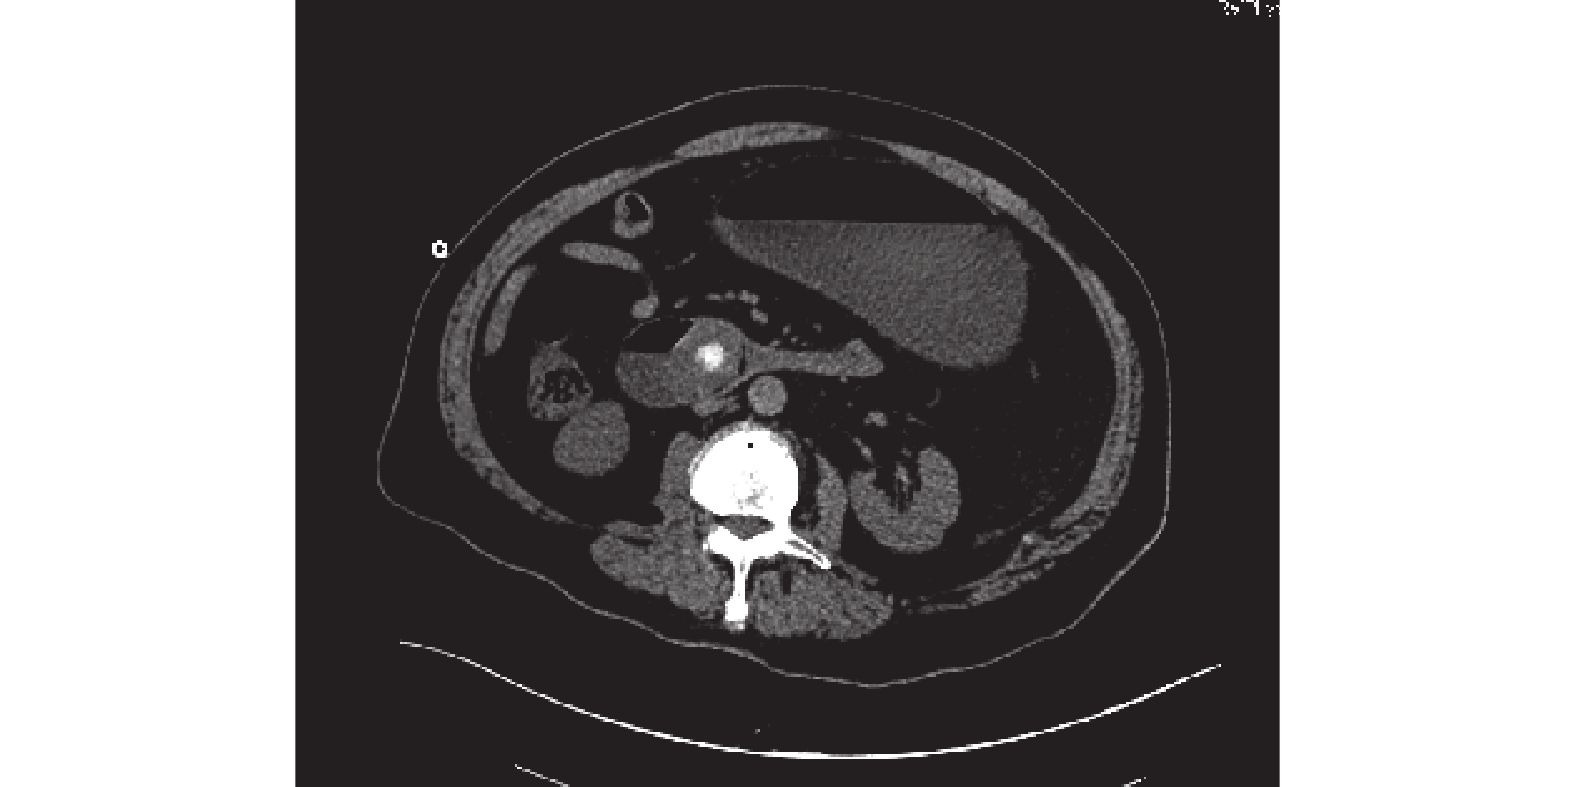

病例資料 患者,男,73 歲,因“進食后嘔吐 5 d、腹痛 1 d”入院。不伴發熱,無黃疸。既往有 10 余年右上腹不適病史,未予重視。入院后查體:皮膚、鞏膜無黃染,腹部膨隆,見胃形,未見腹壁靜脈曲張,未見腸形及蠕動波,腹軟,全腹壓痛,無肌緊張及反跳痛,莫非氏征陰性,肝區無叩痛,移動性濁音陰性,腸鳴音活躍,未聞及高調腸鳴音及氣過水聲。腹部 CT 示:膽囊壁僵硬,不均勻增厚,周圍脂肪間隙模糊,十二指腸降段見高密度結節影,邊緣等密度影,約 3.4 cm×3.0 cm 大小,其遠端腸腔塌陷,上胃腸道明顯擴張、積氣、積液,見氣液平;肝內外膽管積氣,管壁稍增厚毛糙(圖 1)。胃鏡示:十二指腸降段黏膜充血水腫,乳頭遠端可見一巨大圓形異物嵌頓(圖 2),阻塞管腔,內鏡無法通過,質地堅硬,反復嘗試無法取出。初步診斷:急性腸梗阻(結石性);膽囊十二指腸瘺?入院后予胃腸減壓、抗感染、靜脈營養支持等對癥治療 7 d 后,在全麻下行剖腹探查術。術中見膽囊與周圍組織致密粘連,膽囊約 4 cm×3 cm×3 cm 大,膽囊壁厚約 0.4 cm,囊內未見結石,體部與十二指腸球部相通,瘺口直徑約 1.5 cm。胃十二指腸壁增厚、水腫,于十二指腸降部與水平部交界處捫及一約 4.5 cm×4.0 cm×3.0 cm 大結石,膽總管無擴張。行膽囊切除、十二指腸切開取石、十二指腸修補術,術中將十二指腸降部與水平部交界處結石推至十二指腸降球部瘺口處,沿瘺口縱行切開十二指腸降部 3 cm,完整取出結石(圖 3),將胃管通過幽門送達十二指腸切開段下方,全層間斷縫合十二指腸降部切口,修補十二指腸球部瘺口。術后患者恢復良好,于術后 10 d 痊愈出院。診斷:① 急性十二指腸梗阻(結石性);② 膽囊十二指腸瘺。

討論 慢性結石性膽囊炎因結石長期壓迫和炎癥刺激可導致膽囊與相鄰的十二指腸或結腸粘連、穿通形成內瘺,結石可通過內瘺進入腸道堵塞腸管,引起機械性腸梗阻。以膽囊十二指腸瘺最為常見,結石通過內瘺進入十二指腸而引起梗阻,稱為“膽石性十二指腸梗阻(Bouveret 綜合征)”[1],多發生于 65 歲以上老年人,臨床表現無特殊,癥狀主要有惡心、嘔吐、腹痛、腹脹等,查體可見腹部膨隆、腸鳴音活躍等,因其早期癥狀多不典型,發病率較低,極容易誤診[2-3],疾病進展快,致死率遠高于其他病因所致的腸梗阻。臨床診斷多依據于病史、查體、臨床表現和內鏡或影像學征象,患者既往多有慢性膽囊炎的病史。CT 是目前診斷膽石性十二指腸梗阻最常用的檢查方法,主要征象表現為腸管積氣、積液、擴張,膽管積氣及異位結石(Rigler 三聯征)[4-5]。回顧性研究[6]指出,腹部 CT 聯合 X 線(腹部平片及消化道碘水造影)檢查可更好地顯示內瘺大小及位置、結石梗阻部位和腸壁損傷壞死情況,對治療方式的選擇具有指導作用。胃十二指腸鏡對診斷也有一定的輔助作用。本例為 73 歲老年患者,長期右上腹不適未予重視,當出現明顯腸梗阻癥狀才來就診。極少數結石較小的膽石性十二指腸梗阻者可通過保守治療、自行排石緩解,治療方式上主要有內鏡治療和手術治療。內鏡結合體外碎石術適用于年齡較大、病情較重、不能耐受麻醉或手術者,具有創傷小、恢復快等優勢[7-8]。外科手術治療采用腸切開取石術、瘺口修補術和膽囊切除術。當患者不能耐受一期手術也可先行取石術,后期行瘺口修補術及膽囊切除術[7],對于經驗豐富的外科醫生也可選用腹腔鏡下手術[3,9]。本例患者入院時病情重,一般情況差,結石阻塞腸管管腔,內鏡無法通過,質地堅硬,反復嘗試無法取出。入院后予胃腸減壓、抗感染及靜脈營養支持后行一期的膽囊切除、十二指腸切開取石及十二指腸修補術,術后患者恢復好,痊愈出院。膽石性十二指腸梗阻雖然少見,但因其病情進展快、易誤診,因此臨床上需詳細詢問病史、查體并結合影像學表現,一旦確診,根據患者情況采取合適的手術方式及時手術。針對老年性膽囊結石患者尤其是結石較大者,應避免膽腸瘺的發生,建議早期手術治療。